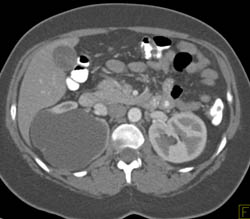

Acute Pyelonephritis With Right Peri-renal Bleed